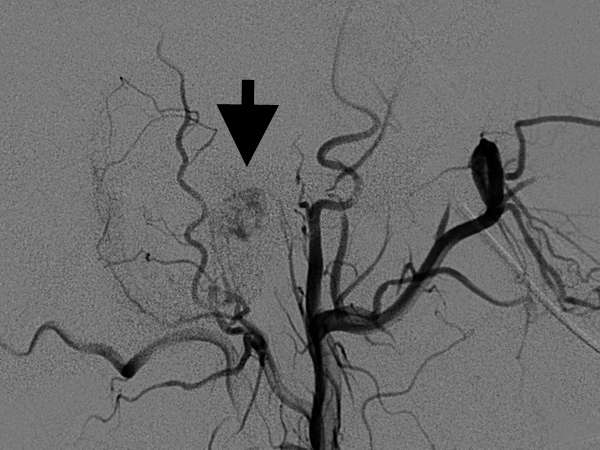

Figure 2: After embolization of small arteries that feed the tumor, the shadow becomes less dense, which indicates the tumor now receives less blood supply.